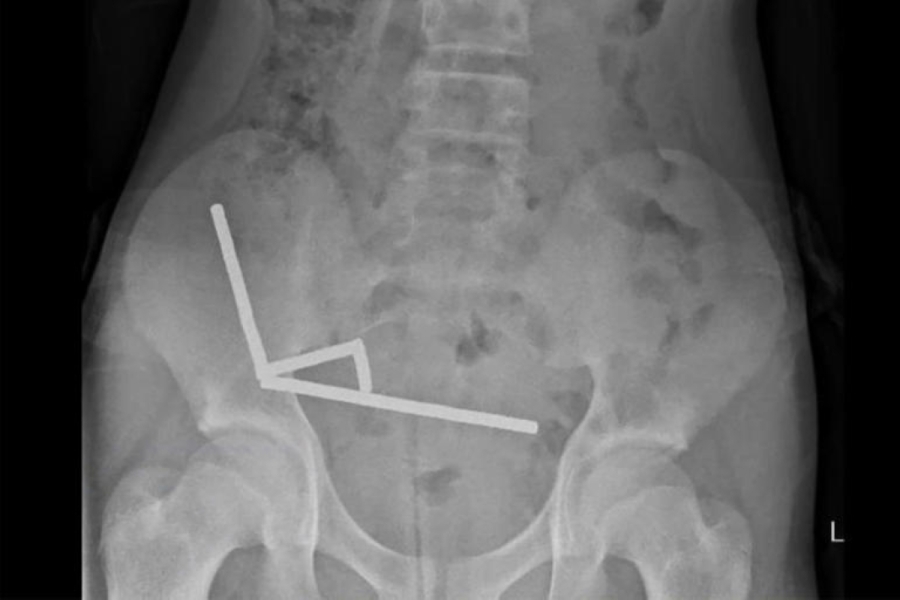

بدأت القصة عندما شعر المراهق بآلام حادة في المعدة، ترافقت مع ارتفاع في درجة الحرارة وغثيان مستمر، مما دفع أسرته إلى نقله على وجه السرعة إلى قسم الطوارئ. وبعد إجراء الأشعة المقطعية، فوجئ الأطباء بوجود مجموعة ضخمة من الكرات المعدنية المغناطيسية داخل الجهاز الهضمي، متشابكة بطريقة تهدد بتمزق الأمعاء.

عملية معقدة استغرقت 8 ساعات

استدعى الفريق الطبي طاقمًا متخصصًا في جراحة الجهاز الهضمي والأطفال، وتم نقل المريض فورًا إلى غرفة العمليات في إجراء طارئ استمر أكثر من ثماني ساعات متواصلة.

وتمكن الأطباء من إزالة جميع الكرات المغناطيسية التي التصقت بجدران الأمعاء، محدثة ثقوبًا دقيقة في بعض المواضع.

وأكد الجراح المشرف أن نجاح العملية كان “أقرب إلى المعجزة” لأن أي تأخير إضافي كان سيؤدي إلى تسمم دموي خطير أو الوفاة خلال ساعات.